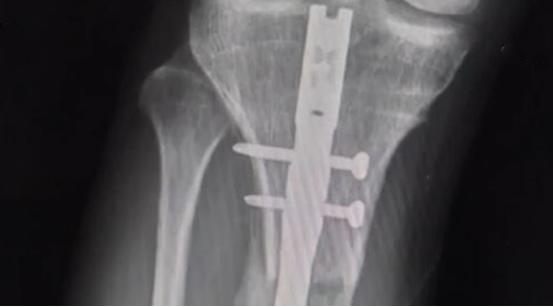

在做手术之前,医生给他进行全面的检查,最终确定术后会增加7.5厘米。

2014年9月24日,李亚诺怀着重生的心,进入了手术室。

这场手术进行了好几个小时,手术结束后,李亚诺被平安地推了出来,

医生告诉他的父母,手术很成功,

如果术后恢复得不错,明年他的身高就能达到174厘米。

在复查的时候,医生告诉他们李亚诺还要做一次手术,这次手术做完后,应该会恢复的不错。

就这样,20岁的李亚诺再次躺进手术室,这一次手术过程进展得很顺利,

然而术后李亚诺的恢复却不为理想。

在拆掉腿部支架后,他的腿部肌肉出现了病变,他再也不能像正常人一样走路了。